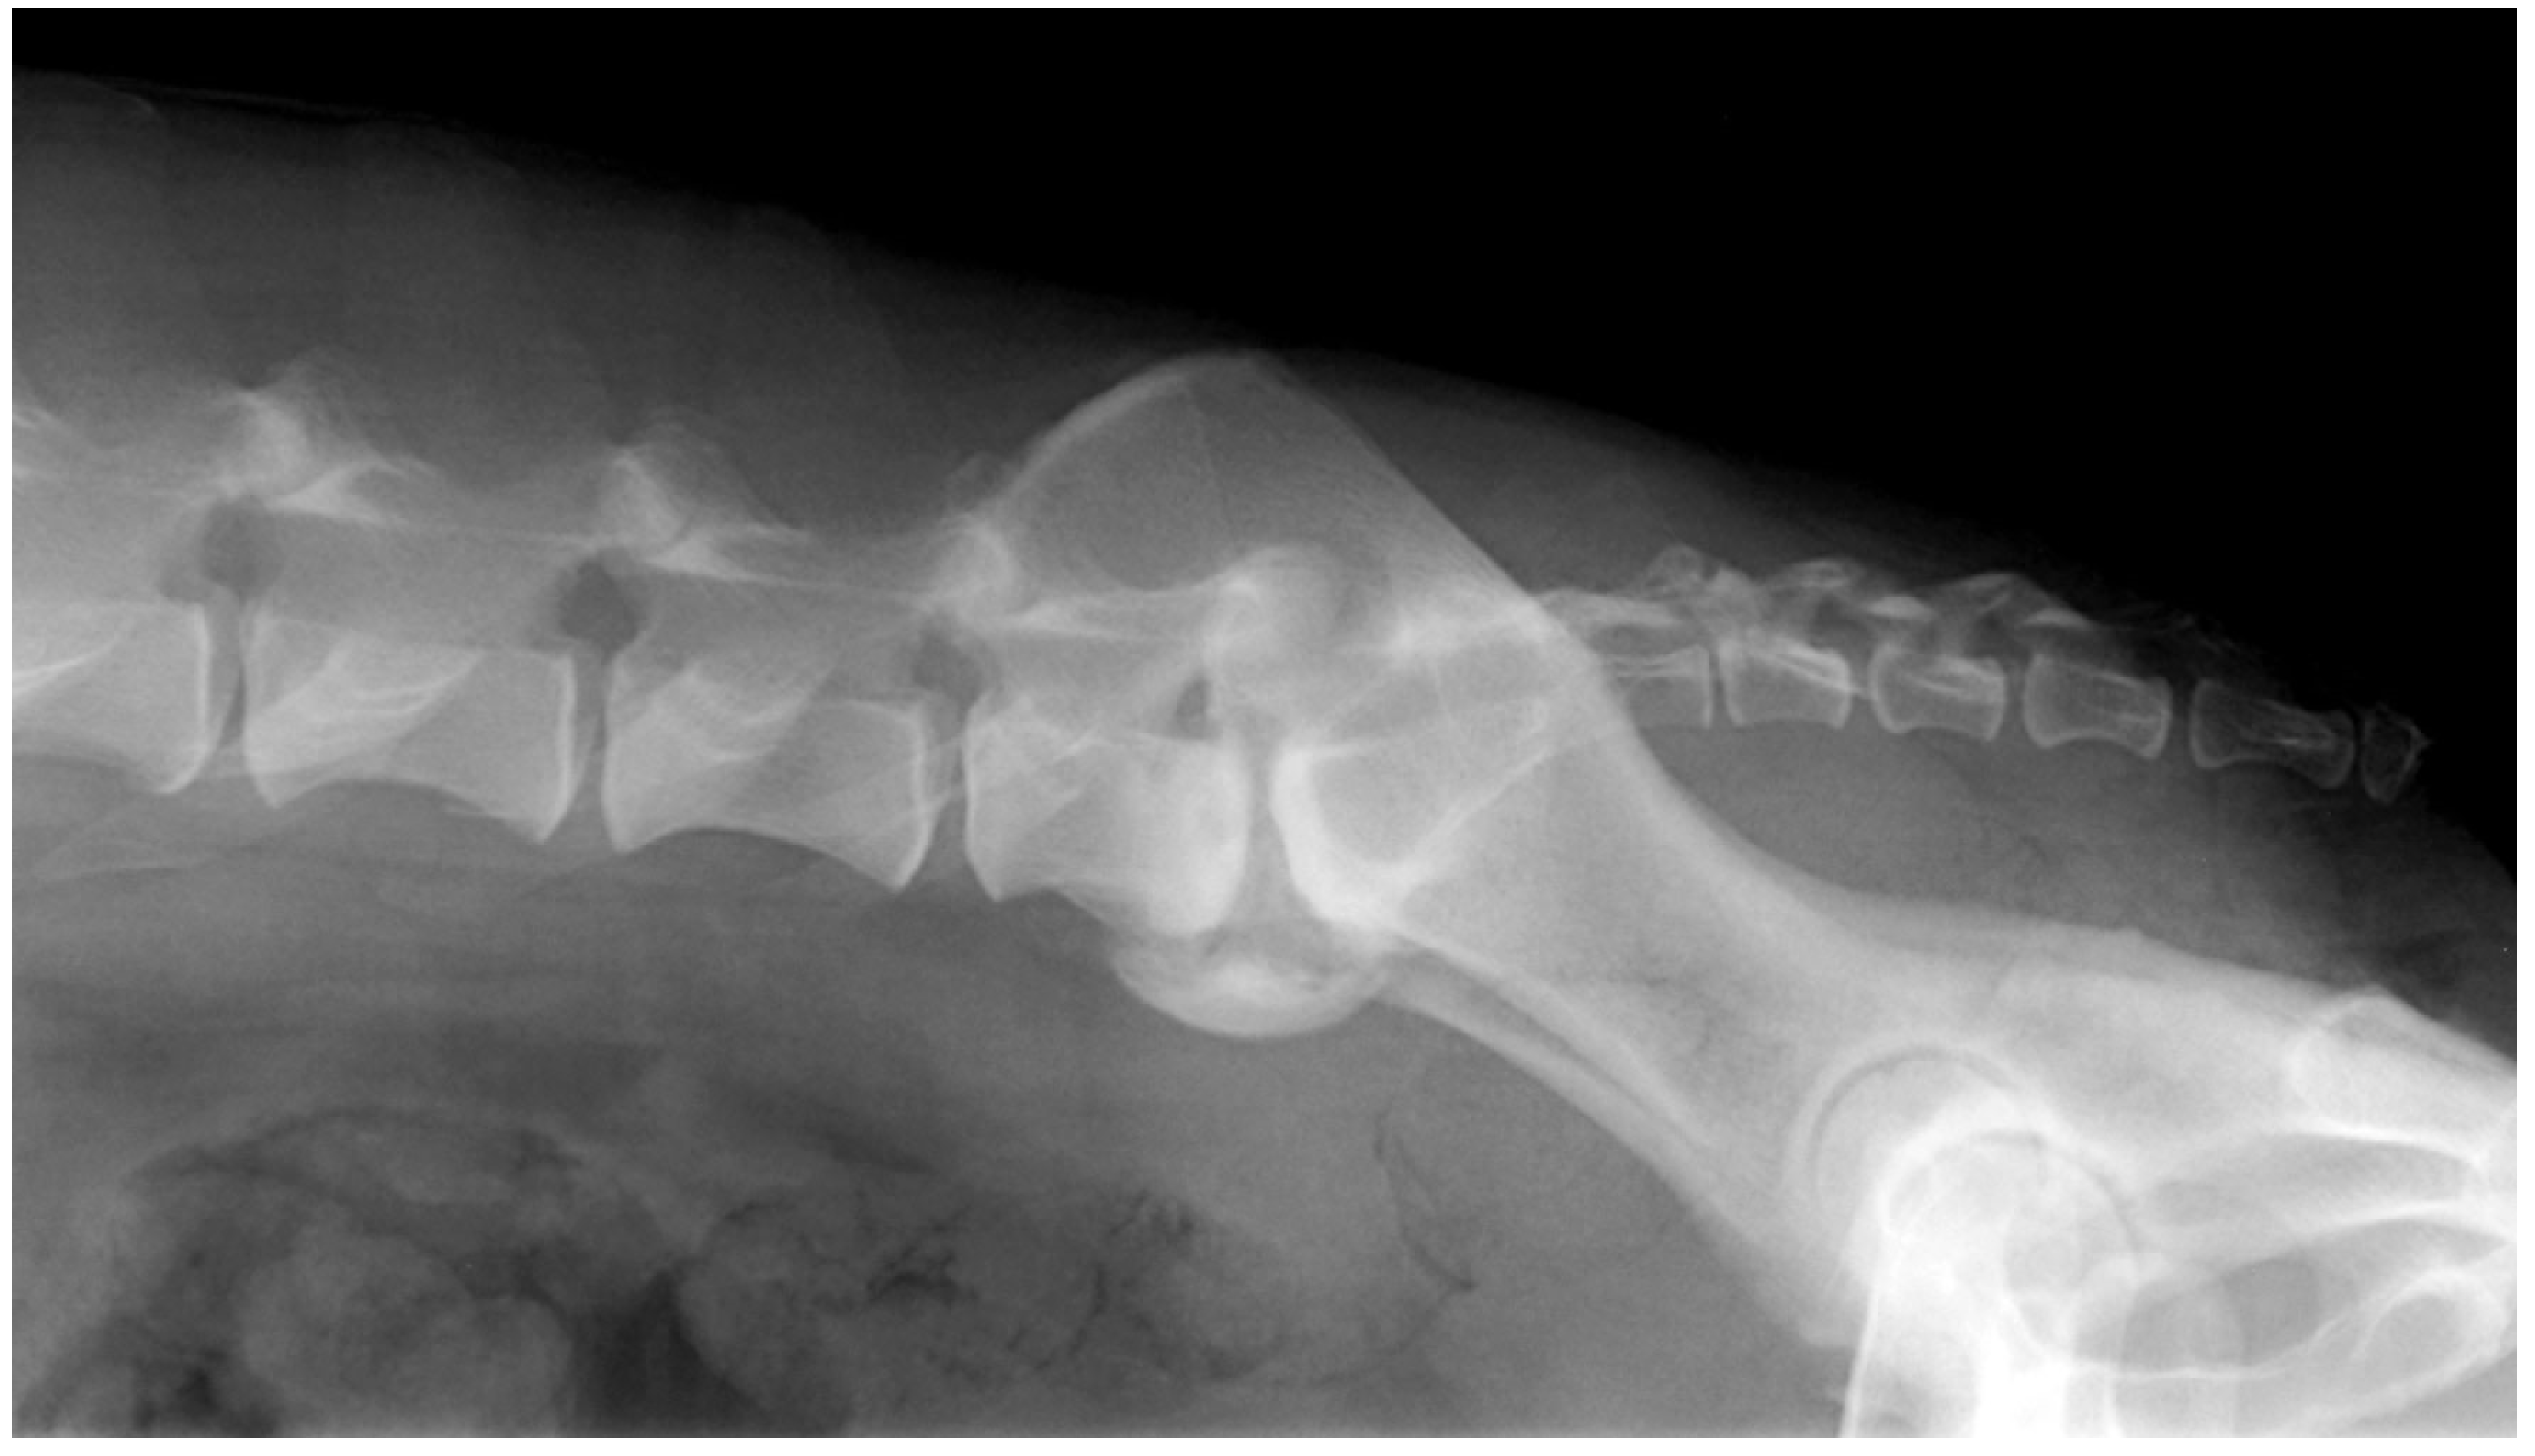

2.2. Imaging Confirmation (X-ray and CT Scan)